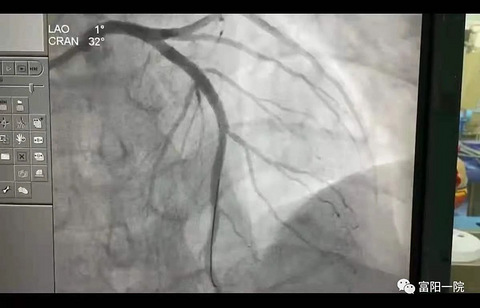

“门诊232+999!”这支队伍在门诊迅速集结,展开分秒必争

“门诊232+999!” “门诊232+999!” “门诊232+999!” …… 4月17日上午,院内广播在富阳一院全院响起,广播呼叫代码的重复播报,引起了全院医务人员及就诊患者的关注! 只见一众白衣天使纷纷从各自岗位迅速赶来!医院究竟发生了什么重大事件?原来一病人在门诊就诊突发心脏骤停,现场晕厥,快速反应团队及就近岗位医护人员在5分钟内集结现场,一场分秒必争的现场急救在门诊232诊室“上演”,